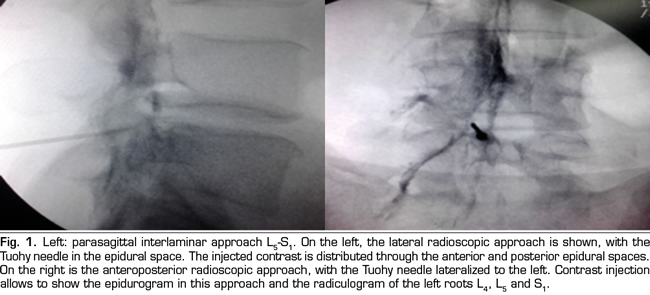

Figure 1